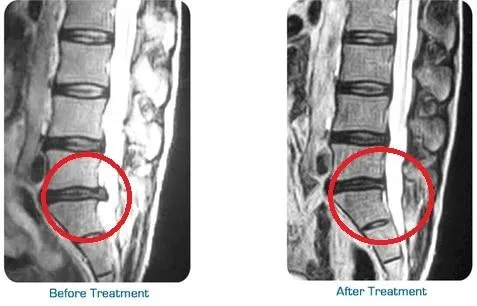

Gently relieves pressure on spinal discs

Improves blood flow and nutrient exchange

Helps reduce pain from herniated or bulging discs

Supports natural healing and recovery

Healthy spinal discs require consistent blood flow to deliver oxygen and nutrients necessary for repair and maintenance. Unfortunately, when discs are compressed, this circulation can be restricted, slowing the healing process. Spinal decompression therapy works to improve blood flow by gently stretching the spine and reducing tension around the discs.

As circulation improves, your body can more effectively deliver essential nutrients to the damaged areas, accelerating the healing process. This enhanced nutrient exchange helps reduce inflammation and promotes tissue regeneration, supporting your spine’s natural ability to repair itself. By restoring proper blood flow, spinal decompression ensures long-term improvements in your spinal health.